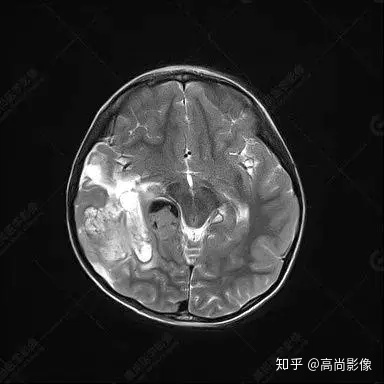

右側(cè)顳葉腫瘤切除術(shù)后(具體不詳):右側(cè)顳部骨質(zhì)不連續(xù)呈術(shù)后改變,右側(cè)顳葉術(shù)區(qū)見片狀長T1長T2信號(hào)影,F(xiàn)LAIR呈低信號(hào);術(shù)區(qū)后方右側(cè)顳枕葉見一巨大占位性病變影,邊界欠清,大小約6.2×5.8×4.3cm(前后×左右×上下),信號(hào)不均勻,T1WI呈等稍低信號(hào)間雜少許高信號(hào),T2WI呈高稍低混雜信號(hào),DWI示部分病灶彌散受限,相應(yīng)ADC圖減低,磁敏感序列見部分呈極低信號(hào),增強(qiáng)掃描可見明顯不均勻強(qiáng)化,鄰近硬腦膜及小腦幕增厚并明顯強(qiáng)化;另延髓右前方及右側(cè)橋小腦角區(qū)見一不規(guī)則形異常信號(hào)影,大小約3.2×1.3×3.7cm(左右×前后×上下),呈長T1稍長T2信號(hào),F(xiàn)LAIR呈等信號(hào),DWI未見受限,增強(qiáng)后明顯均勻強(qiáng)化,鄰近腦膜明顯強(qiáng)化。鄰近腦實(shí)質(zhì)及右側(cè)顳角明顯受壓;左側(cè)大腦半球未見局灶性信號(hào)異常,中線結(jié)構(gòu)稍左移。

右側(cè)顳葉腫瘤切除術(shù)后:現(xiàn)術(shù)區(qū)后方右側(cè)顳枕葉及延髓右前方占位,右側(cè)顳枕部硬腦膜及小腦幕明顯強(qiáng)化,結(jié)合既往影像資料,考慮為胚胎源性惡性腫瘤,如非典型畸胎樣/橫紋肌樣瘤(AT/RT)或原始神經(jīng)外胚層腫瘤(PNET)。